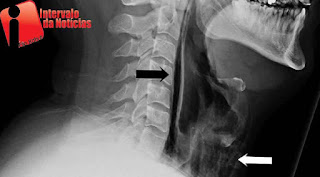

Um jovem rompeu a garganta e ficou quase sem fala após segurar um espirro. O caso foi publicado no “British Medical Journal Case Reports”, do periódico BMJ, que costuma publicar casos atípicos da medicina.

De acordo com o relato, o homem tampou a boca e apertou o nariz na tentativa de conter um espirro. Desta forma, acabou com uma fratura grave na parte de trás da garganta. Os médicos que atenderam a vítima classificaram o caso como ‘surpreendente’, já que esse tipo de ruptura só é vista em traumas e em acidentes.

A fratura foi seguida de dores intensas e bolhas de ar passaram a invadir tecidos, levando o jovem à internação. No hospital, o homem foi alimentado por tubos e recebeu antibióticos até ser liberado sete dias depois.